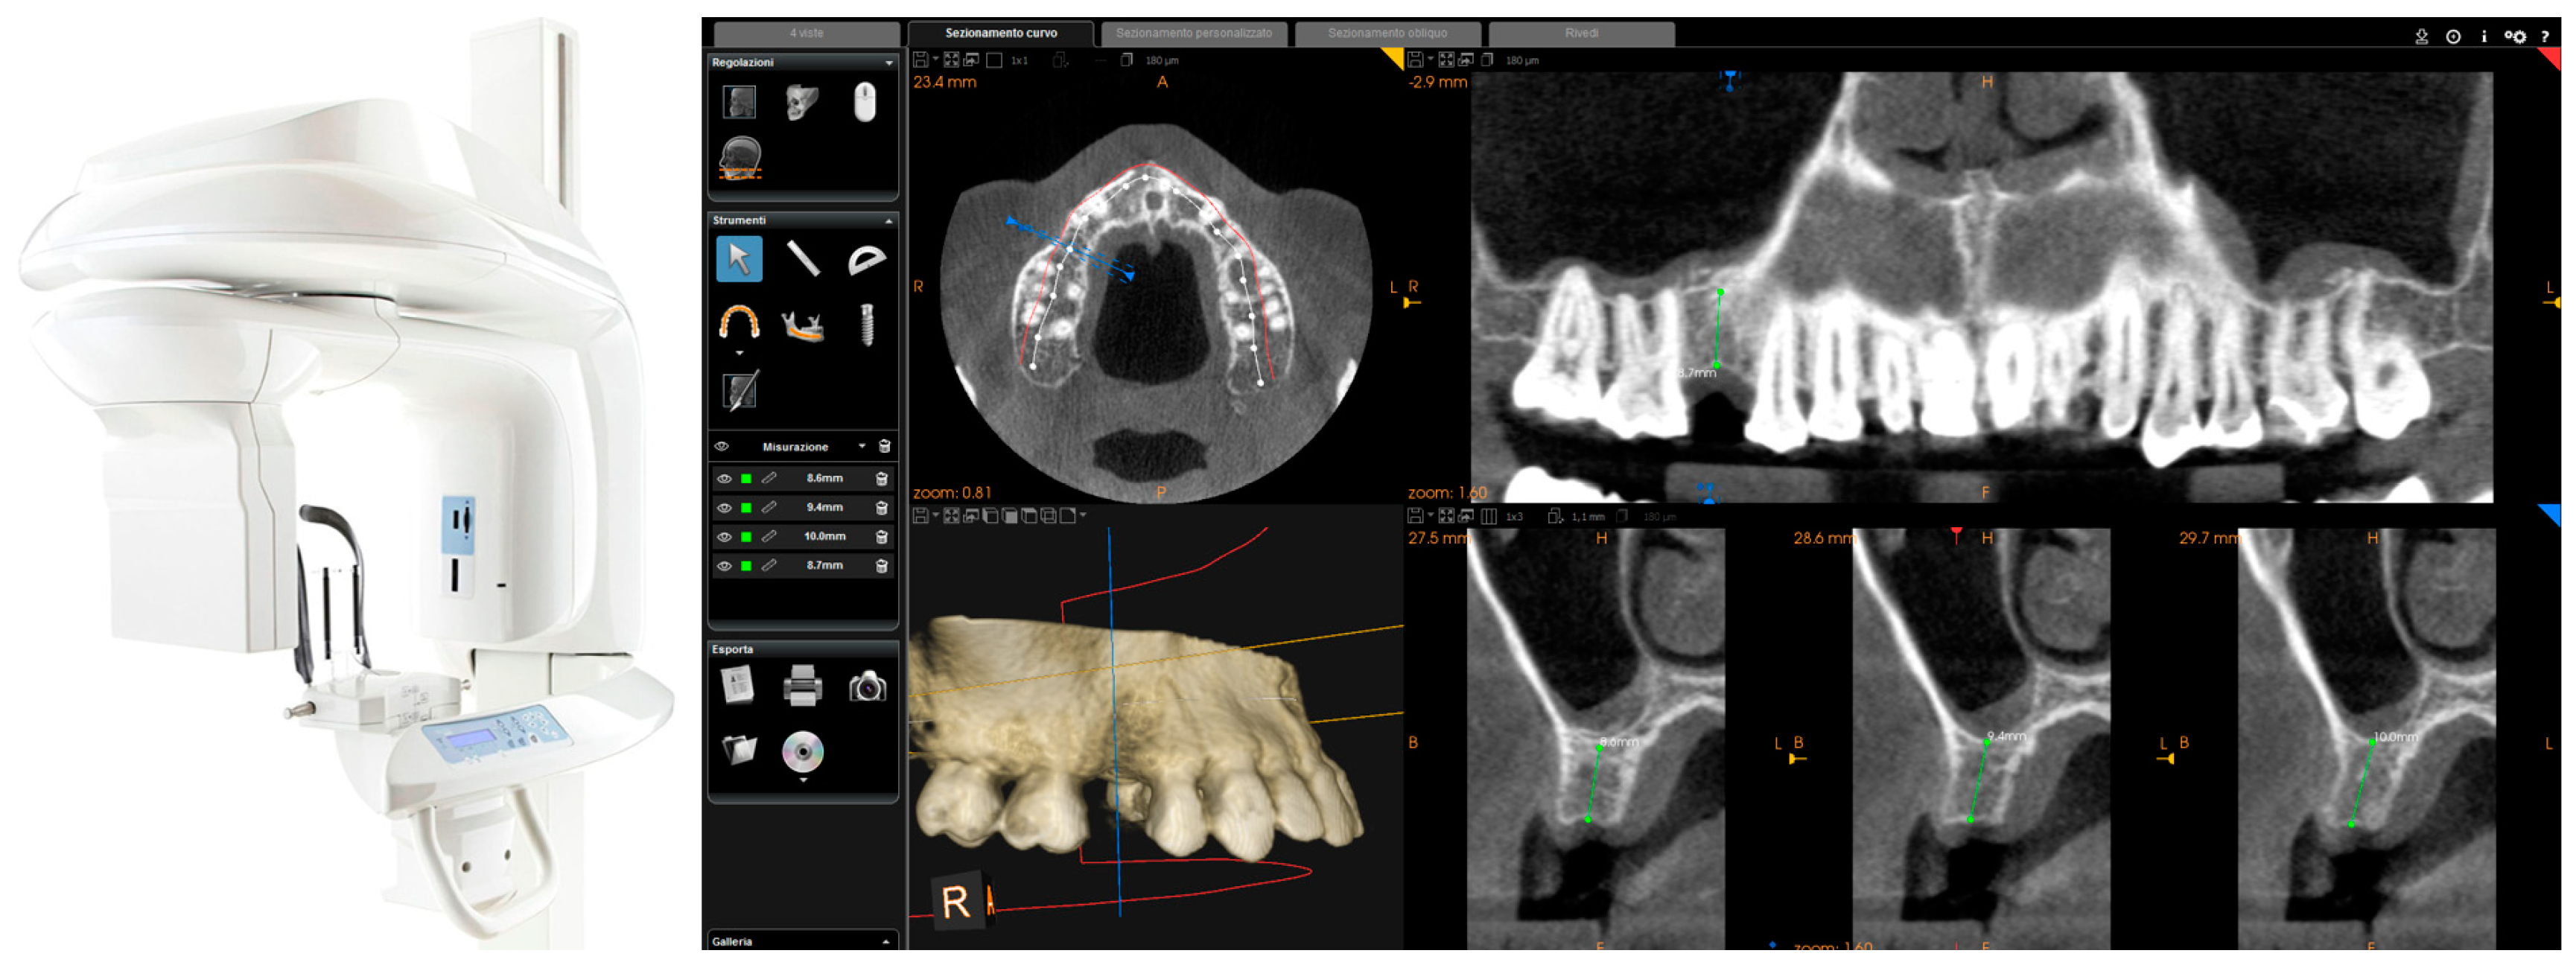

Each of the patients selected for inclusion in the present prospective study was subjected to intraoral scan of the arches, with a powerful structured light scanner (CS 3600®, Carestream Dental, Atlanta, GA, USA) (Figure 1).

Figure 1.

Intraoral scan CS 3600® (Carestream Dental, Atlanta, GA, USA). The second right premolar (#15) is missing and an implant is going to be planned. (A) Occlusal view. (B) Lateral view.

This scan was performed in orthodontic mode, and consisted of a scan of the master model (site of the edentulism), of the antagonist, and of the capture of the bite (occlusion). During the scan, the operator took care to capture every morphological detail of the teeth adjacent to the implant, i.e., those selected to support the future surgical guide. At the same time, special attention was paid to the scanning of soft tissues in the area of edentulism. The files thus acquired were saved in .STL format in a special folder. In the same session, the patient was then subjected to 3D radiological examination with cone beam computed tomography (CBCT), using a powerful scanner with adjustable field-of-view (CS 9300®, Carestream Dental, Atlanta, GA, USA) (Figure 2).

Figure 2.

CBCT with CS 9300® (Carestream Dental, Atlanta, GA, USA). The first visualization of the CBCT reveals sufficient bone volume (height and width) to plan the position of a dental implant.

The operator was therefore able to select the more appropriate field of view (FOV) for the case (usually 10 × 5-cm FOV, to facilitate the overlap with the model derived from intraoral scanning, in the presence of metal artefacts, but in some cases without artifacts, even a 5 × 5-cm FOV) and then capture the patient’s 3D bone anatomy, which was immediately displayed in the CBCT reconstruction software. Particular attention was paid before the radiological examination to the centering of the area of interest, through specific dedicated tools; then, great attention was placed during the scan, so that the patient did not make any movement, and was completely immobile. After a first rapid visualization of the site of interest, and a first rapid measurement of the height and thickness of the residual ridge, confirming the feasibility of the case, the digital imaging and communication in medicines (DICOM) files derived from the CBCT were saved in a specific folder and were ready to be imported into the guided surgery software.